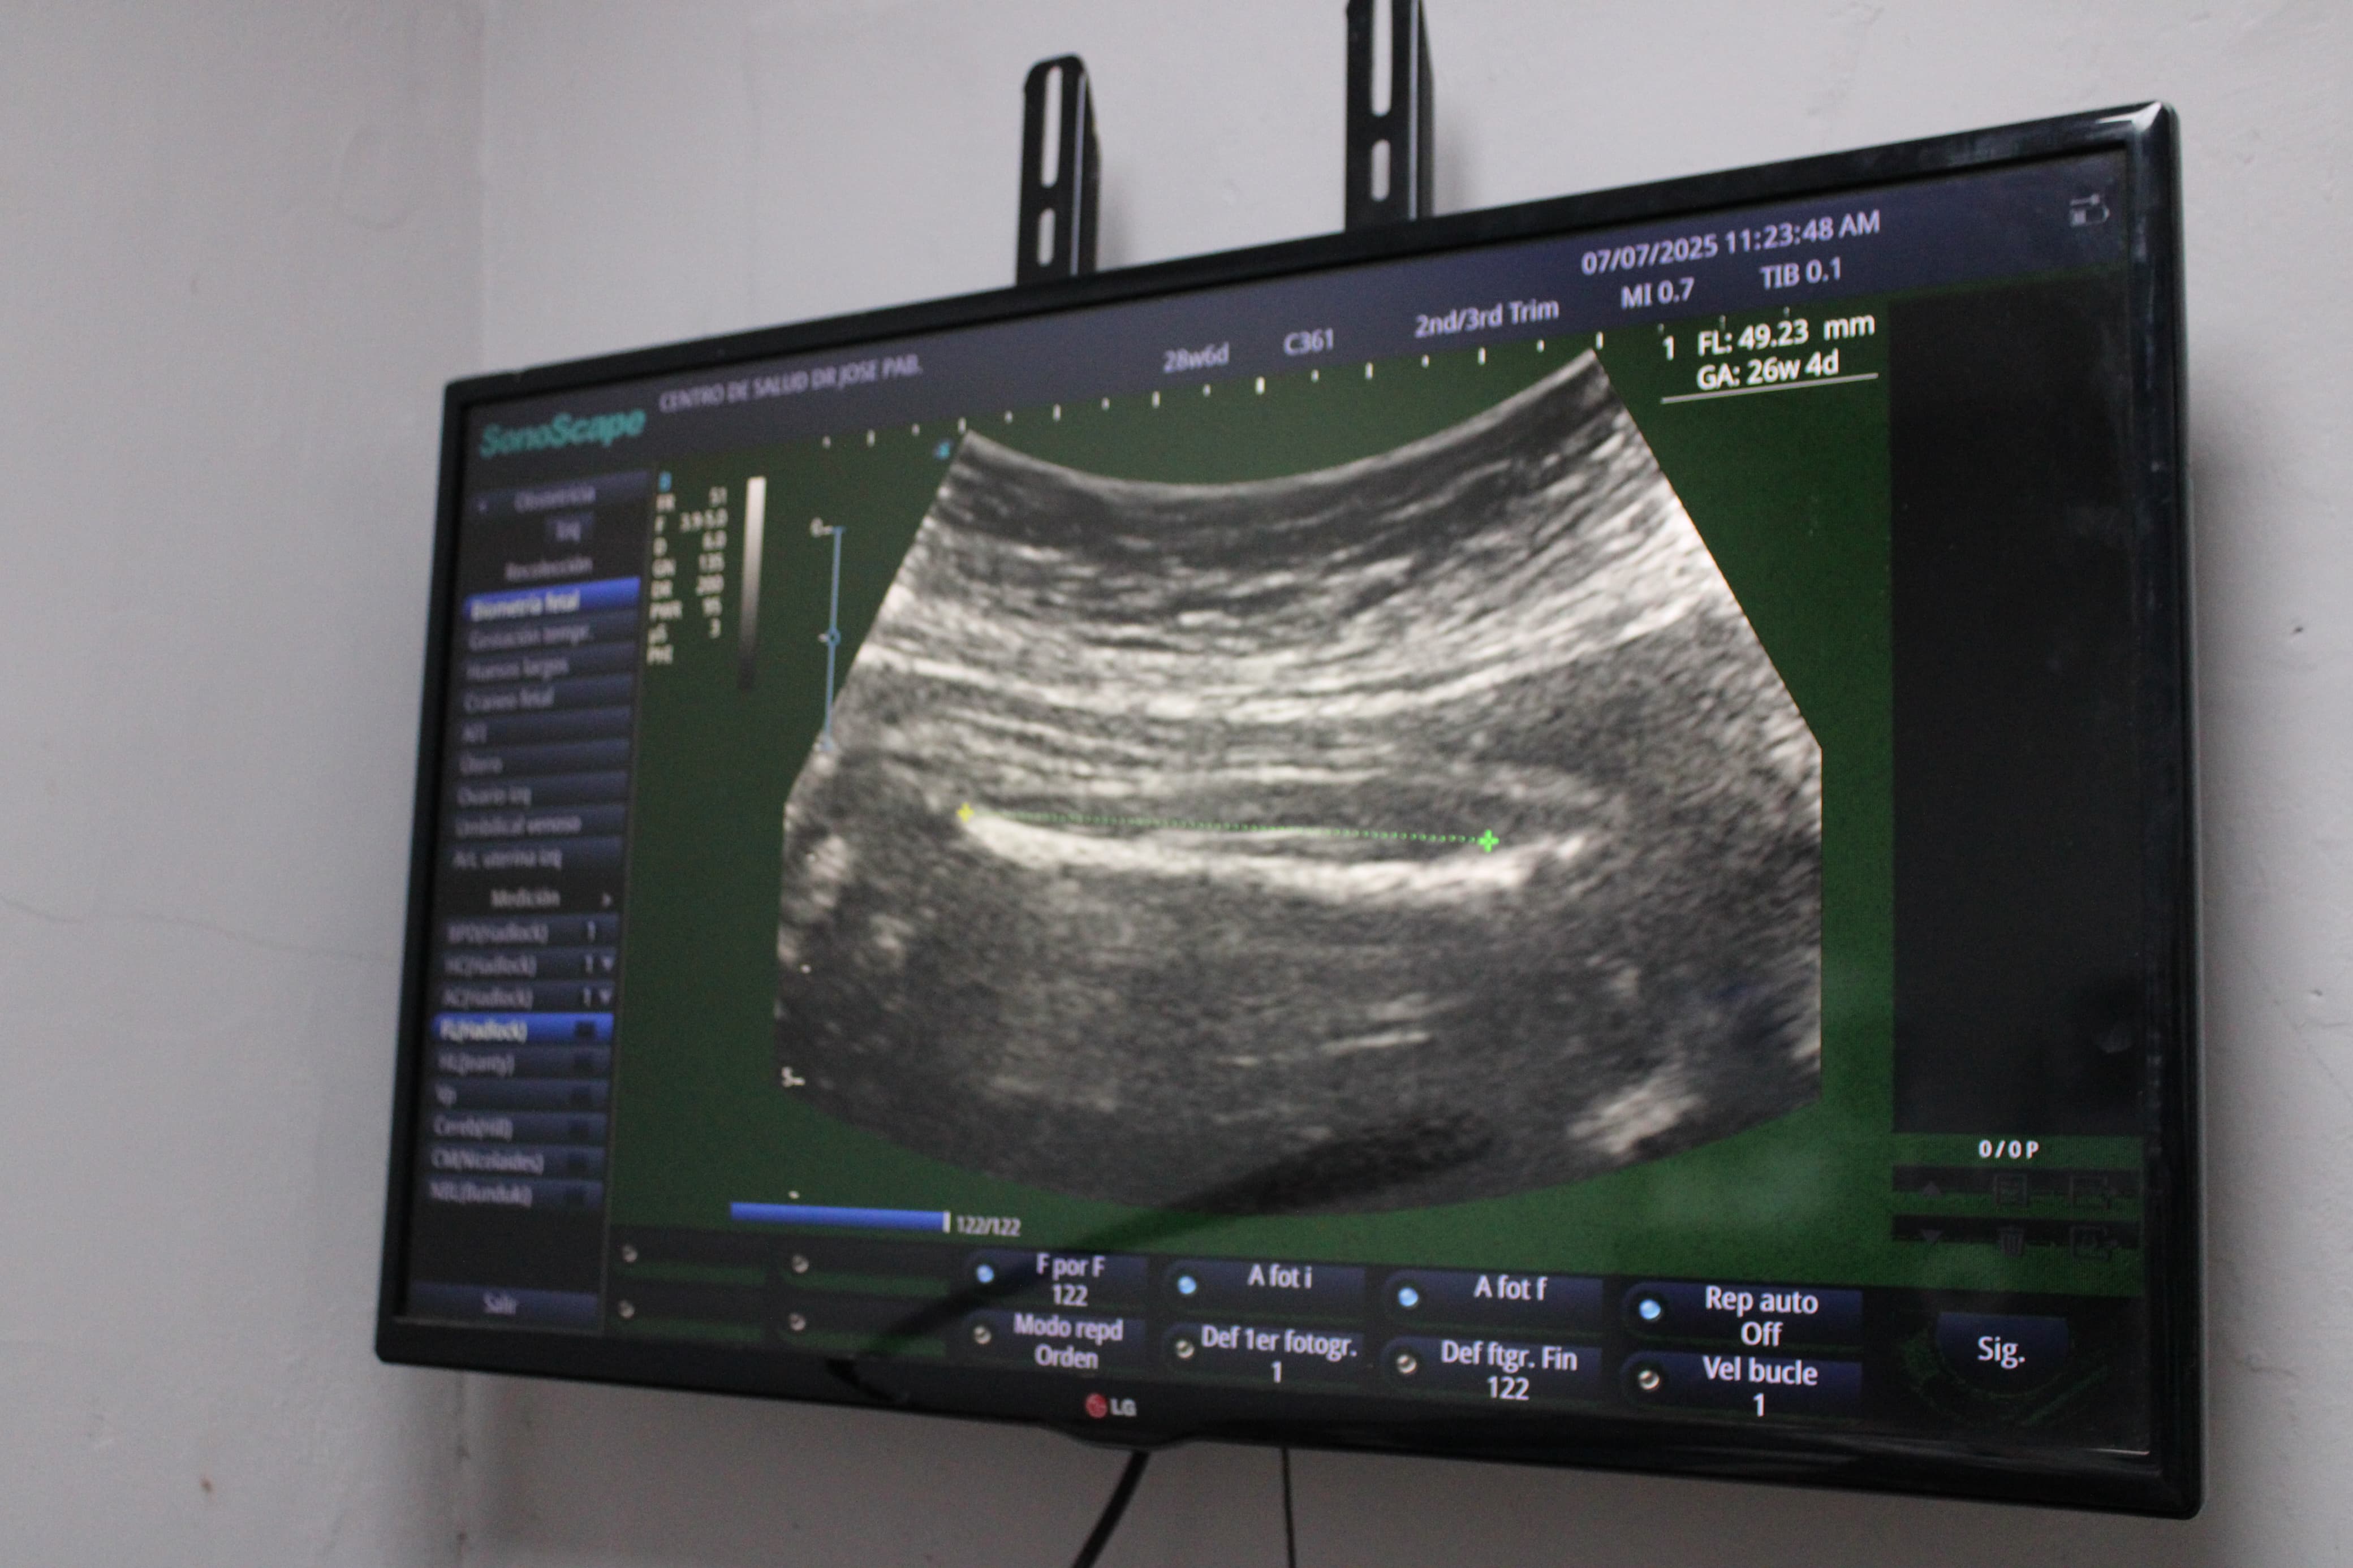

El nuevo equipo es un Sonoscape portátil E1 Expert, representa una inversión de 10 mil balboas y está diseñado para ofrecer imágenes de alta calidad que faciliten un mejor seguimiento del embarazo desde el primer hasta el último trimestre, permitiendo detectar oportunamente cualquier complicación y reforzando así la atención preventiva.